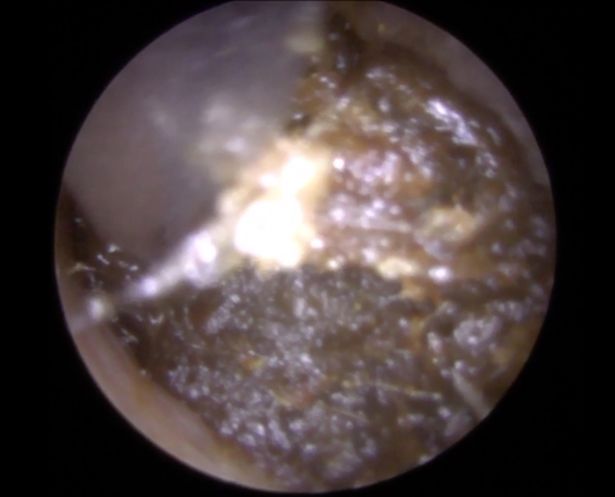

如果你有一些老的醫生朋友,他們應該都有一些很恐怖的故事可以分享吧?這位來自英國的Raithatha醫生就在自己的YouTube頻道上,分享了這段他說是「最慘最慘的耳屎」(我覺得可以叫噁屎了…) 一般清理耳朵只需要花醫生5分鐘的時間,但他卻花了10分鐘… 他表示做這行10年來第一次碰到那麼棘手的狀況…

現在這段影片已經超過百萬觀看數,他說:「因為這次的耳屎黏太緊,他根本不可能自己挖出來,我覺得這次的耳屎主要原因是長期用棉花棒清理,但不小心把耳屎都推到裡面去了,這也是為什麼我們不建議大家用棉花棒的原因。」好啦,來看看最慘的耳屎是什麼樣子的吧! 注意:畫面有點噁…(影片須點開至youtube觀看)